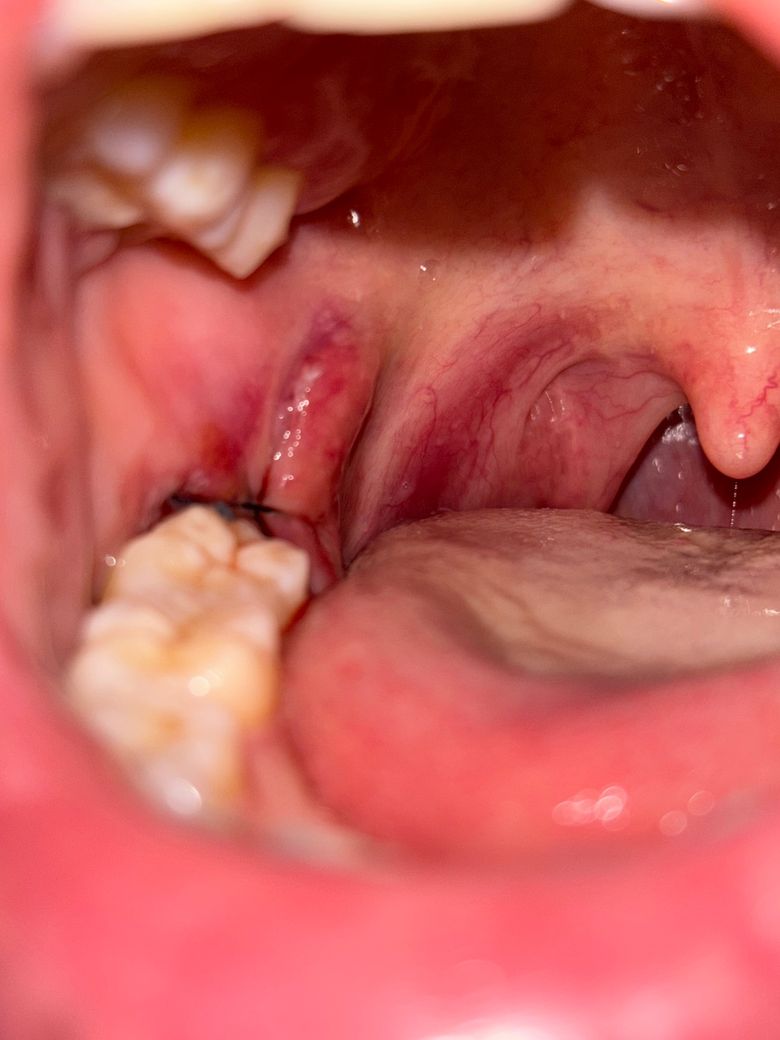

사랑니 발치 후 거울로 입안을 봤더니 사진과 같이 볼쪽까지 째서 뽑으셨더라구요. 근데 사랑니 뺀 부분만 꼬매놓으셔서 볼 쪽은 점점 더 붓고, 째진 부분이 달랑달랑 거리고 씹혀서 불편합니다. 완전 매복도 아닌데 절제 범위가 원래 이렇게 넓나요?ㅜㅜ 가만히둬야할지 약이라도 발라야할지 고민입니다..

• 3번 째 사진

사랑니 발치시 매복이 깊은경우에는 절개 범위가 생각보다 넓습니다. 저정도 잇몸절개를 하는게 맞습니다.

사랑니를 뽑을 때 시야 확보를 위해서 잇몸 절개를 더 하는 경우도 있습니다. 잇몸은 대부분 일주일 정도 지나면 아물기 때문에 크게 문제가 되지는 않습니다.

사랑니가 위치한 게 수직이어서 그렇지 완전매복 맞습니다. 더 원활한 발치를 위해 절개를 크게 한 것 같습니다